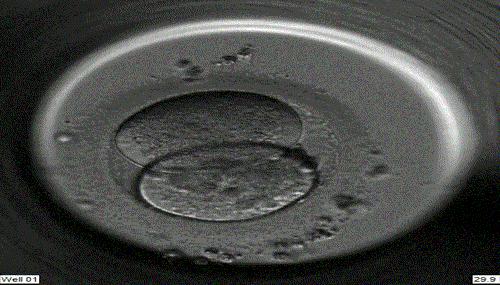

受精

取卵后将处理后的精子与卵子放在同一个培养皿中,共同培养18小时后,可在显微镜下观察受精情况。若精子质量太差,无法自然受精,则需以显微注射法显微注射受精 即卵胞浆内单精子显微授精。

俗称第一代试管婴儿,使精子和卵子在培养皿中自然受精。